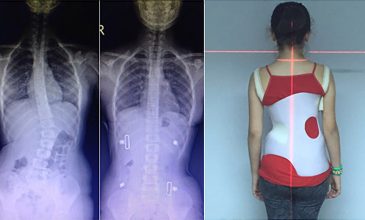

BAŞLANGIÇ X-RAY

skolyoz1

BAŞLANGIÇ POSTÜR

skolyoz2